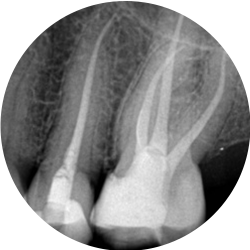

Endodontics is the branch of dentistry which is concerned with the morphology, physiology and pathology of the human dental pulp and periradicular tissues. Its study and practice encompass the basic clinical sciences including biology of the normal pulp; the etiology, diagnosis, prevention, and treatment of diseases and injuries of the pulp and associated periradicular conditions.

Bacteria associated with decay, deep restorations, fractures, trauma or periodontal disease may irreversibly damage the pulp. In order to preserve a tooth, in which this has occurred, it is necessary to remove the injured, infected tissue. This procedure is known as root canal therapy.